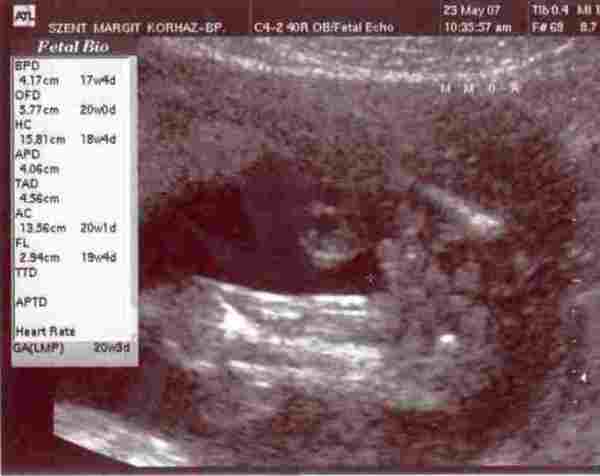

Tegnap voltam a Margit kh-ban az AFP eredményért. AFP 55,7, MOM 1,4, ami jónak számít.

Ezenkívül voltam genetikai uh-n is. Mindent rendben találtak. Az is kiderült, hogy

fiunk lesz :) Mostmár gondolkozunk a neveken…

Megpróbálok feltenni néhány fotót bizonyítékként. Valamint, amin én meglepődtem, hogy 2d-s metszetben milyen jól kivehető az arcocskája. Nagy élmény volt. De azért elmegyünk hamarosan 4d-sre is. A vizsgálatot egyébként nem csapta össze a szonográfus, nagyon kedves volt, és mindent megnézett. Szerintem kb. 20 percet lehettem bent.

Most egyébként azt mondták, hogy inkább a 19. hétben vagyok, mint a 18-ban.

A 18 hetes uh eredményen nálam ac, fl, hc, bpd és ofd eredmények vannak. Súlybecslés alapján 275g. Még nemigazán tudom, mit jelentenek ezek, de mindenképpen utánanézek.

Ha sikerül beszúrnom, akkor a felvételeken látható:

1. baba arca: szeme, orra szája

2. a keresztnél három pötty a kukija (herék+pénisz), középen

3. a kukija felnagyítva, hosszában

Baba arca

háát, feltöltve nem olyan jó minőségűek a képek, de talán kivehető.